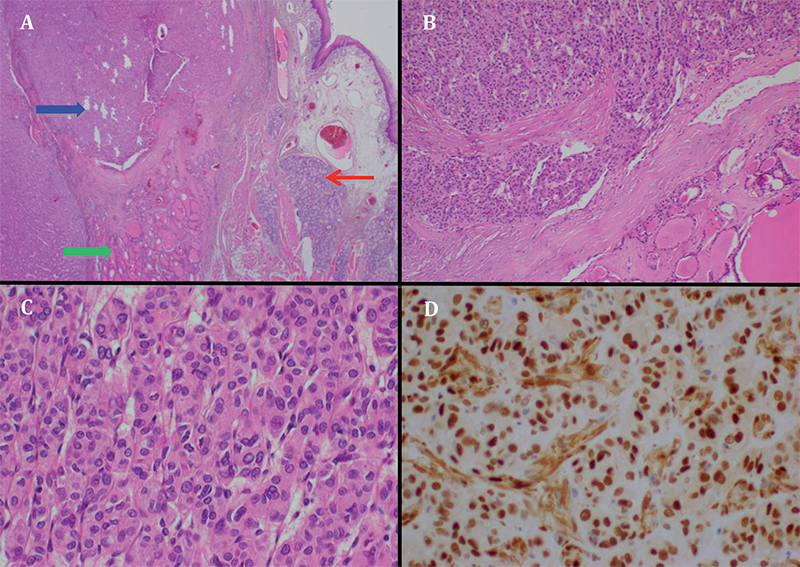

Mujer de 23 años, fumadora de 2 paquetes/año, con antecedentes de hipotiroidismo desde los 20 años en tratamiento con levotiroxina, subtratada. Consulta por cuadro de 5 meses de evolución caracterizado por odinofagia leve y sensación de cuerpo extraño orofaríngeo, asociado a episodios de sangrado bucal de mal olor. Se realiza nasofibroscopía encontrando en línea media una masa redondeada en la base de la lengua cuya biopsia describe neoplasia tiroidea con patrón sólido y ulcerada que infiltra la cápsula tumoral sin traspasarla (Figura 1A y 1B) constituida por células epiteloideas de gran tamaño formando nidos, cordones, trabéculas y áreas sólidas con núcleos irregulares atípicos (Figura 1C). La Inmunohistoquímica demostró: Factor 1 de Transcripción Tiroidea (TTF-1) (+), Ciclina D1 (+), Citoqueratina 7 de membrana en células tumorales (+), HBME -1 (+), Focal de algunas células tumorales, Citoqueratina 20 (-), CEA(-) y Sinaptofisina (-) (Figura 1D) RM cervical muestra ocupación de la vallécula por tejido de partes blandas, de estructura discretamente heterogénea de baja señal en T1 e hiperintenso en T2 que se impregna tras la administración de gadolinio, de 20 x 20 x 22 mm en los ejes mayores y que desplaza la epiglotis hacia caudal. No se visualiza glándula tiroides en el opérculo toráxico ni región cervical anterior (Figura 2A y B). En cintigrama tiroideo se observa concentración del radiofármaco sólo en un área ovalada de localización sublingual en la línea media (Figura 2 C) concluyendo presencia de TTE. Ecografía cervical confirma lecho tiroideo vacío (Figura 2D) y un nódulo sólido hipoecogénico de 19 x 20 x 20 mm en base de la lengua (Figura 2E) sin evidencia de extensión locorregional. Se presenta en Comité de Tiroides, indicándose cirugía. En el procedimiento se ve y palpa tumor en base de lengua de aproximadamente 40 mm de diámetro mayor, friable, bastante superficial, bien delimitado. Se secciona la lengua en línea media, se identifica tumor resecándolo completamente. La biopsia definitiva concluye carcinoma folicular mínimamente invasor con dos permeaciones vasculares. Se indica radioablación con 100 mCi de I-131, el rastreo sistémico a los 7 días fue negativo. Los valores de TSH y Tg se presentan en Tabla 1. Actualmente la paciente está en seguimiento bajo terapia de sustitución con levotiroxina, eutiroidea desde el punto de vista clínico y de laboratorio.